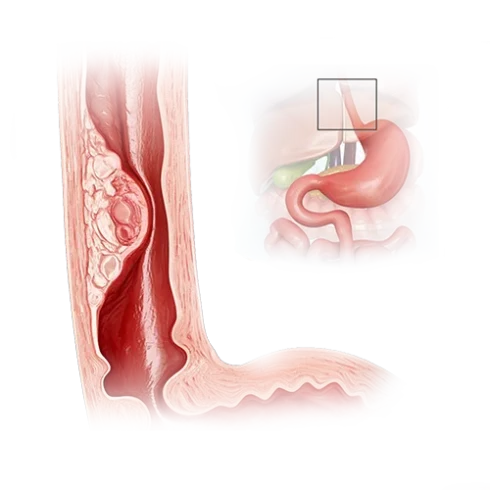

食管癌是一种恶性肿瘤。其发生源于食管黏膜细胞的异常突变,随着时间的推移,疾病不仅会扩散至食管壁的各个层次,还会沿着食管蔓延。肿瘤逐渐阻塞食管腔,阻碍食物通过,导致患者出现消瘦,严重时甚至死亡。

- 2023 年 2 月 6 日,CT(胸腔+腹腔增强)提示胸段食管中三分之一处存在肿瘤,直径 14×12 mm;肝右叶见单个转移灶(18×16 mm)。

- 食管镜活检证实癌症,组织学结果为食管鳞状细胞癌。